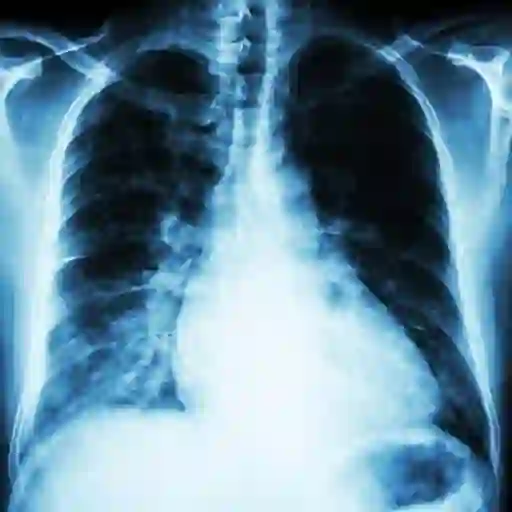

胸部X射线

iStock

得到诊断

您的血液将进行钠的测试(低水平表明血液中的水过多),钾(低水平与中风,高血压和心脏病有关)以及其他可能表明心脏损伤的生物标志物。Contreras博士说,胸部X射线射线可以揭示您的肺部是否有液体或心脏肿大(表明您的心脏肌肉正在加班以抽血的迹象)。根据这些结果,您的医生可能会订购其他测试,包括运动应力测试,心电图,超声心动图和/或MRI。